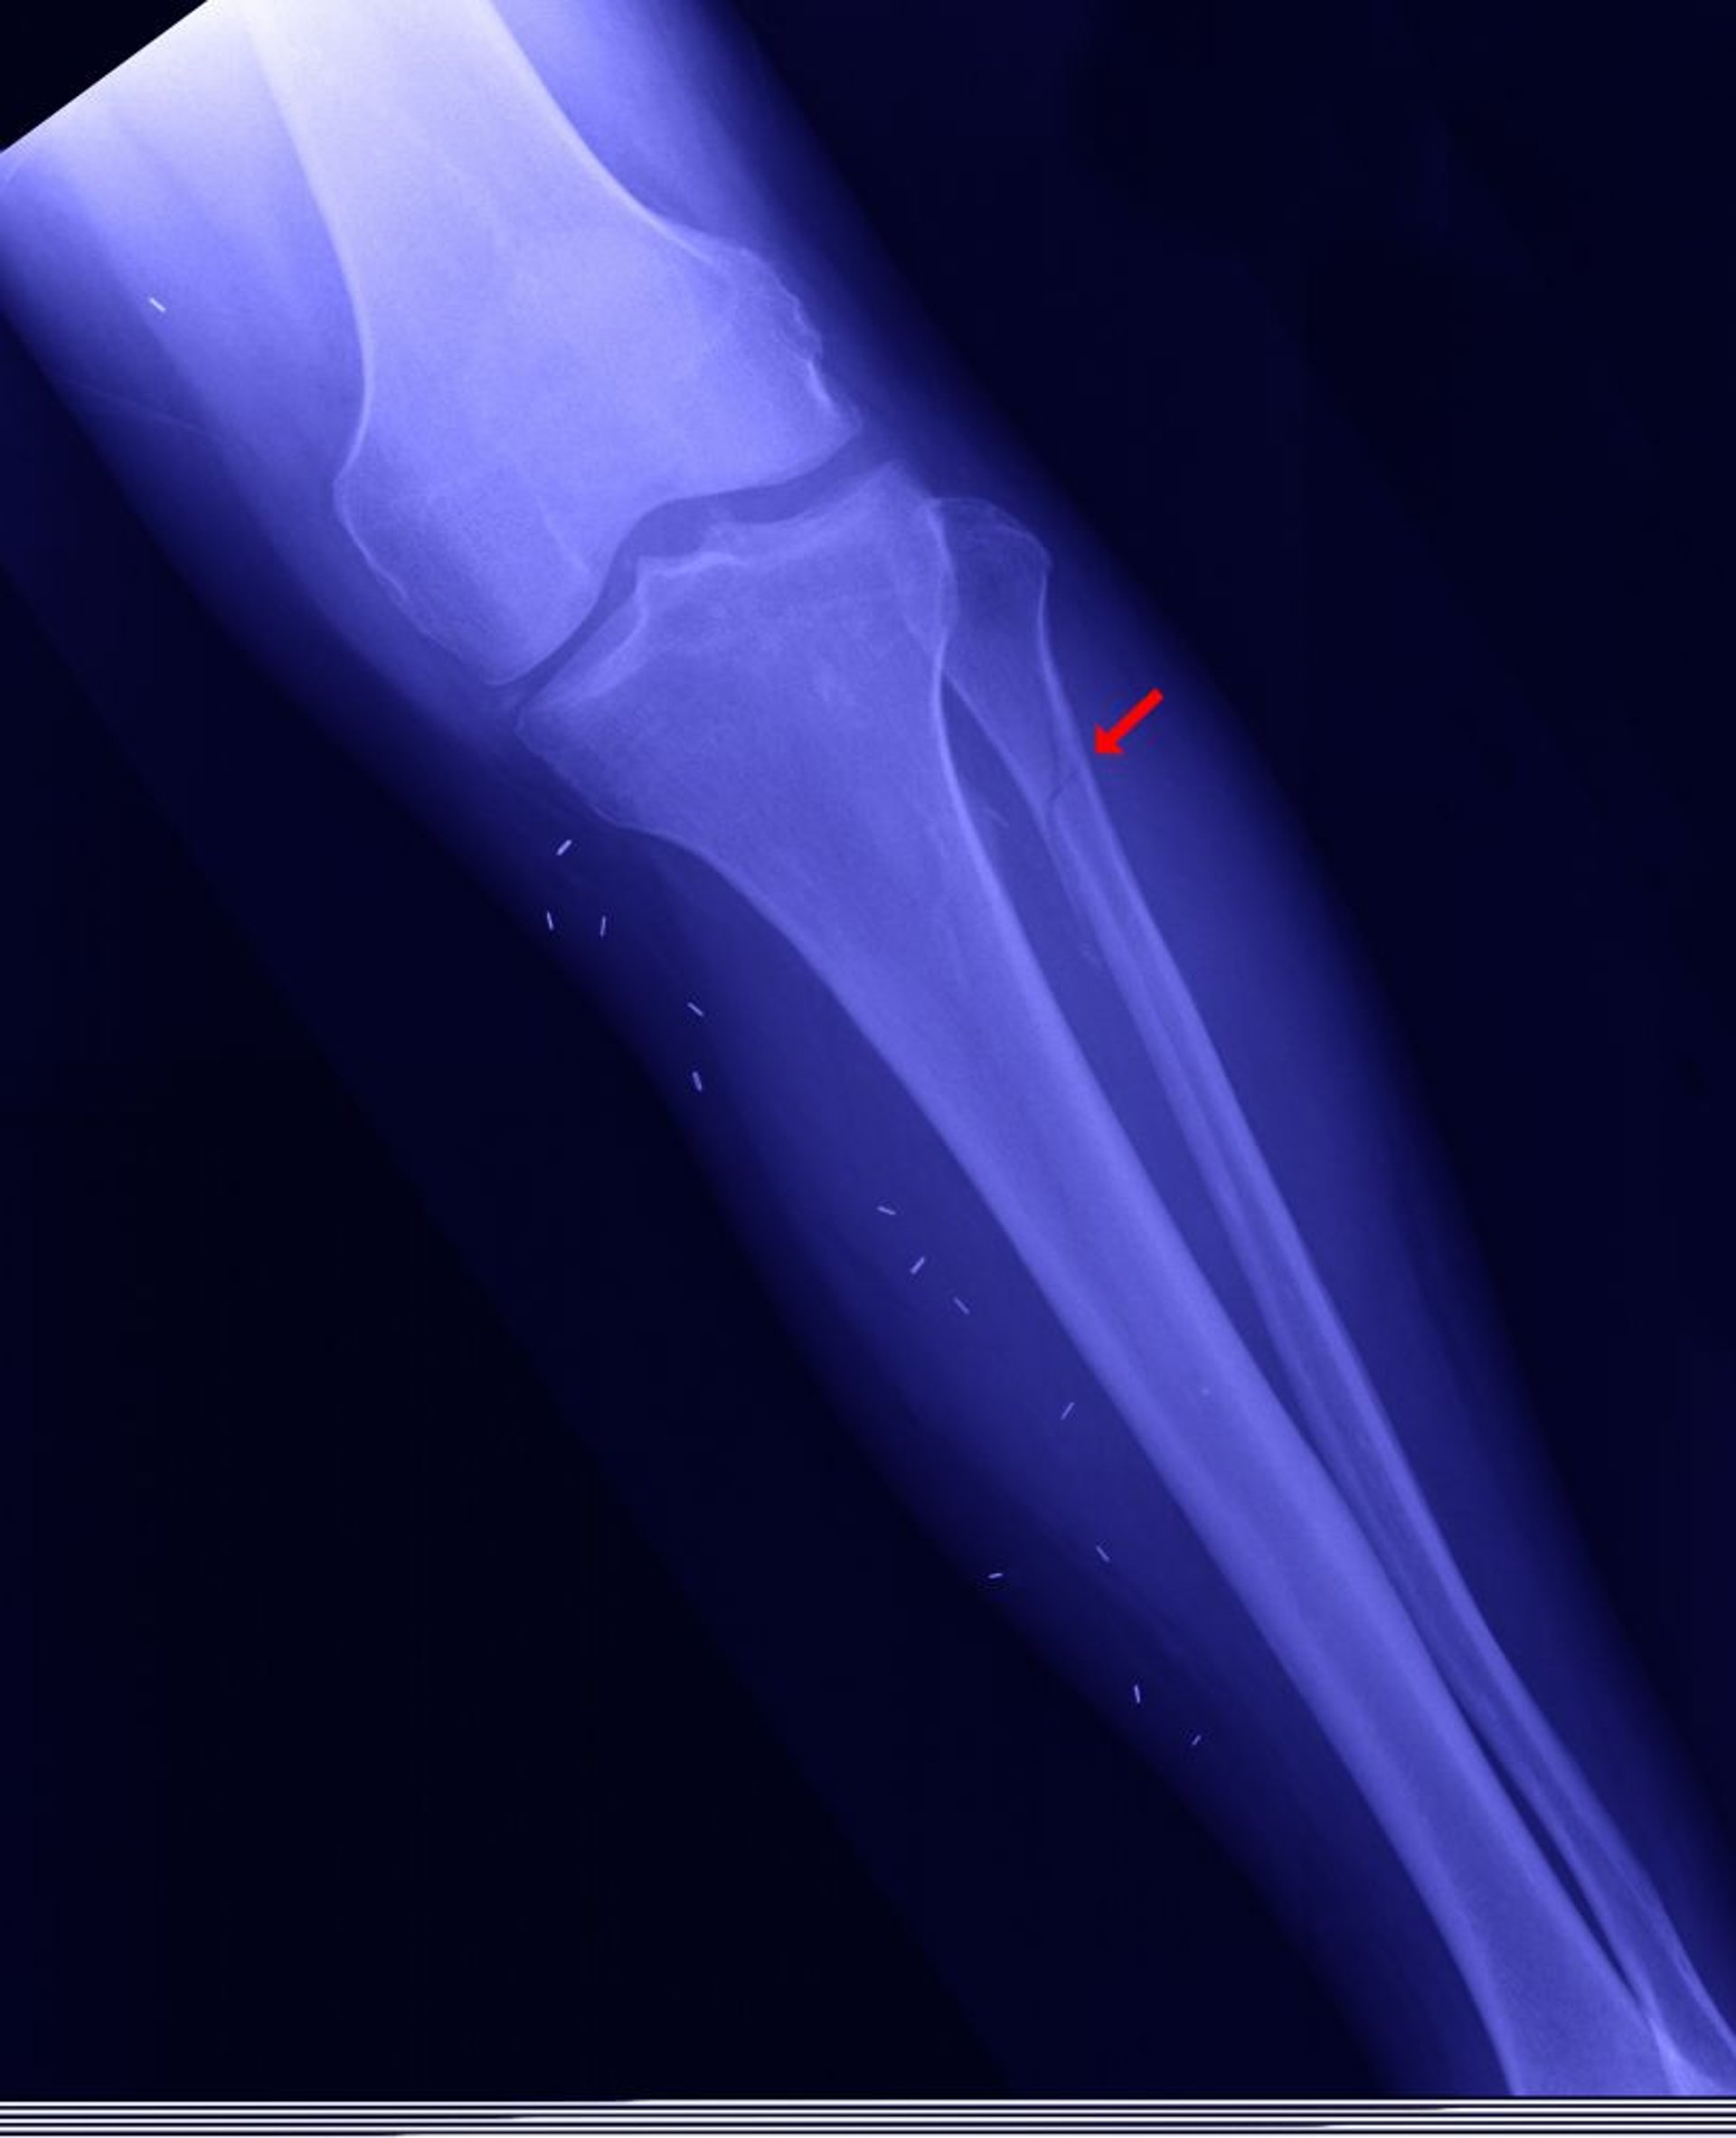

Перелом проксимального отдела малоберцовой кости

Проксимальный отдел малоберцовой кости может быть сломан (так называемый перелом Мезоннева показан здесь), когда медиальная лодыжка сломанная, межберцовый паз (место соединения между голенью и таранной костью) открыт, а дистальный отдел малоберцовой кости не сломан.